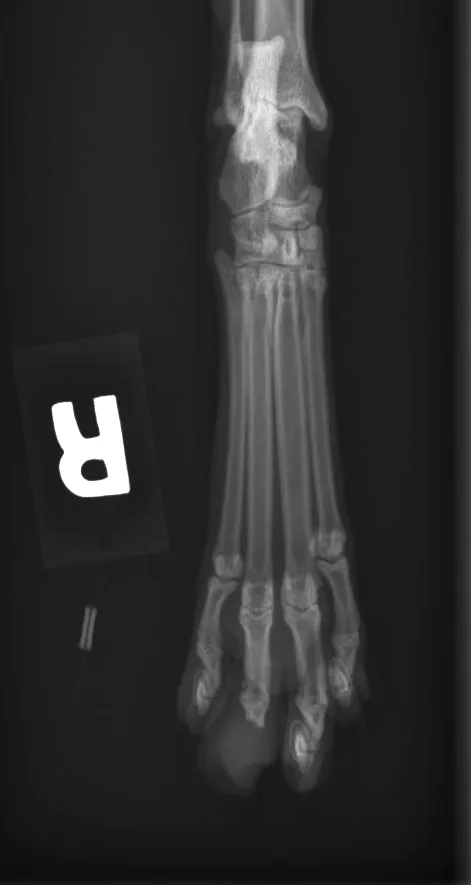

One dorsal–plantar view of the tarsus and foot of the right pelvic limb was obtained (Figure 1). A lateral view was not obtained because of the likelihood of low diagnostic yield (ie, superimposition of digits 2–4). The toes can be separated with gauze or string for a lateral view, but this patient was too painful to do so without analgesia/sedation.

Dorsoplantar x-ray view of a cat’s hind foot.

FIGURE 1

Soft tissue swelling surrounded the phalanges of the right pelvic limb third digit. The entire distal phalanx of the third digit was absent, and the distal portion of the middle phalanx of the third digit was lytic.

Aggressive bone lesion of the distal and middle phalanges of the third digit. Aggressive bone lesions can be secondary to neoplasia or infection. Absence of periosteal proliferation and the degree of lysis makes neoplasia more likely than infection. The involvement of two adjacent bones also suggests a soft tissue origin of malignancy (primary bone tumors rarely cross joints). Metastasis of pulmonary carcinoma to the digit is well documented1-3 and should be a strong differential at this point.